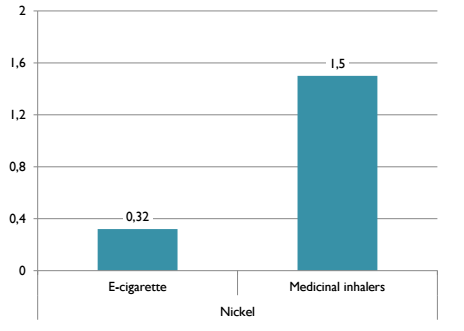

Однако эти значения довольно незначительны. Для сравнения, Доктор Фарсалинос сопоставил их содержание с разрешимым в медицине порогом для медицинских ингаляторов:

- Никель